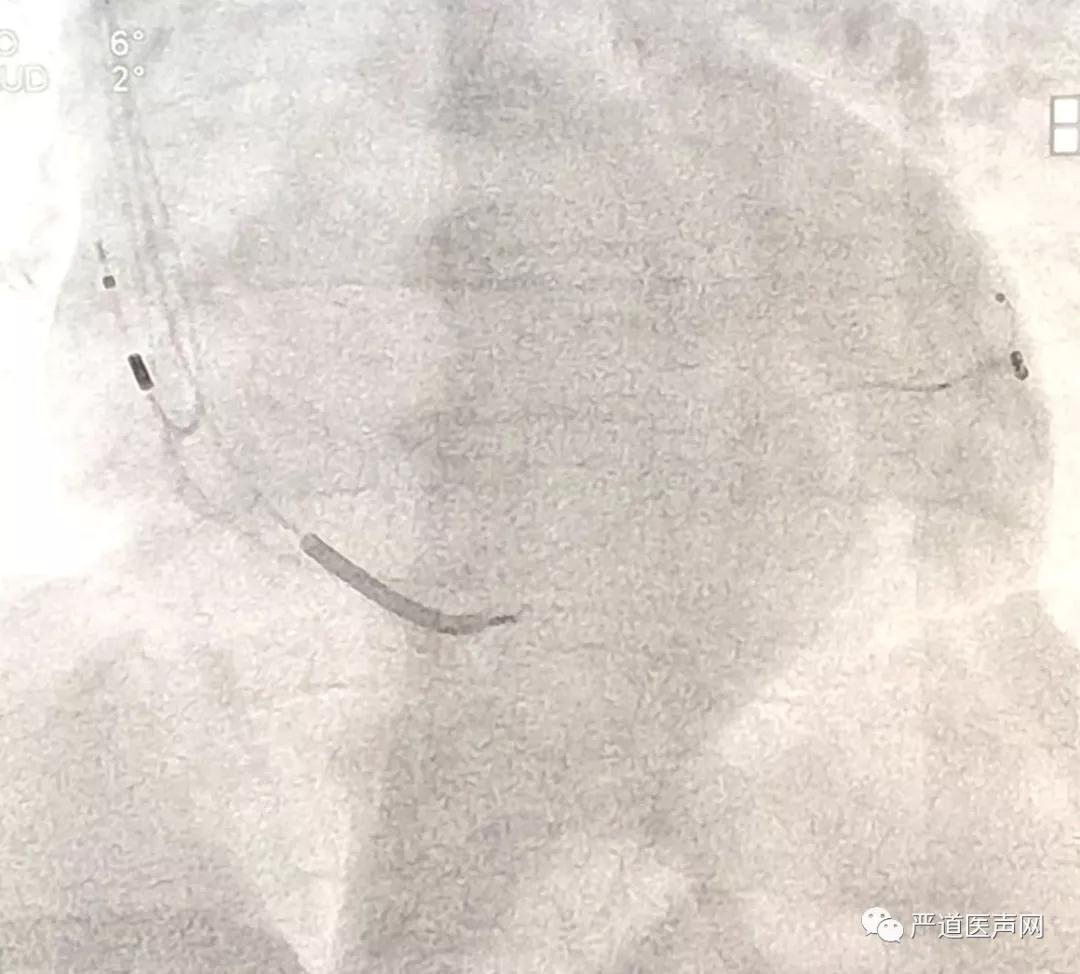

X4导线植入靶静脉

术中,严激教授为学员们讲解了CRT植入的标准操作步骤,对每一处需要注意的细节和操作要领进行了详细说明。本例患者的冠状窦开口部位存在一定阻力,为了增强外鞘管的推送力,严激教授采用EP导管寻找冠状窦并成功辅助外鞘管进入,静脉造影发现鞘管直接超选了患者的侧静脉,根据血管的走行情况,严激教授选择了波士顿科学ACUITY X4 Spiral S左室四极导线,这种导线具有远端叉齿和近端3D螺旋的双重固定设计,能够帮助导线更好的固定在血管远端。术中测试发现X4导线上四个电极的阈值均在正常范围内,无膈神经刺激出现。